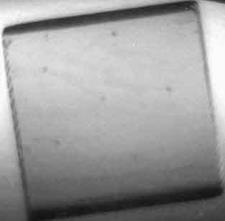

Для количественных оценок параметров маммографических диагностических аппаратов используются специально разработанные фантомы, которые представляют собой восковую пластину с различными включениями, имитирующими опухоли. На Курчатовском источнике СИ К.М.Подурец с сотрудниками выполнил эксперимент [5], используя сертифицированный фантом RM156, и показал, что использование рефракционного метода значительно повышает чувствительность метода и позволяет обнаруживать такие объекты, как микрокальцинаты, кальцинированные сосуды и опухоли в несколько раз меньшего размера, чем при стандартной, абсорбционной съемке (см. рис.3). Новый тип контраста в сочетании с высоким качеством пучка синхротронного излучения дает возможность не только повысить информативность изображений, но и значительно снизить дозовую нагрузку на пациента. Было также установлено, что если слегка пожертвовать информативностью изображений за счет уменьшения времени экспозиции, удается при стандартном уровне обнаружения признаков заболевания дополнительно снизить дозу облучения при обследовании.

Рис. 3. Изображения фрагментов фантома, моделирующих микрокальцинаты (а), кальцинированный сосуд (б) и опухоль (в).